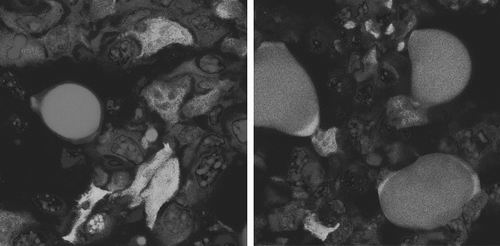

图片来源:《细胞》

当这些小鼠接受两种美国食品药品监督管理局批准的药物—— 一种癌症抑制剂和一种抗糖尿病药物治疗时,这些侵袭性癌细胞会转化为脂肪细胞。这些药物还能抑制小鼠体内原发性肿瘤的生长,并防止肿瘤向全身扩散。